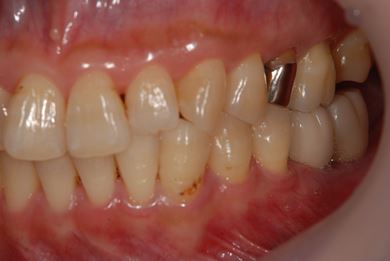

インプラントの症例写真 IMPLANT

インプラント治療

| 性別/年齢 | 女性 / 46歳 | ||||||||||||||||||||||||||||||||

| 主訴 | 左奥歯のインプラント治療を希望。 | ||||||||||||||||||||||||||||||||

| 治療方針 | 左下奥、欠損部分をインプラント治療にて、機能的・審美的回復を行う。 | ||||||||||||||||||||||||||||||||

| 治療内容 | インプラント2本、ハイブリッドセラミッククラウン2本 | ||||||||||||||||||||||||||||||||

| 総治療費 | 399,000円 | ||||||||||||||||||||||||||||||||

| 治療期間 | 5ヶ月 |